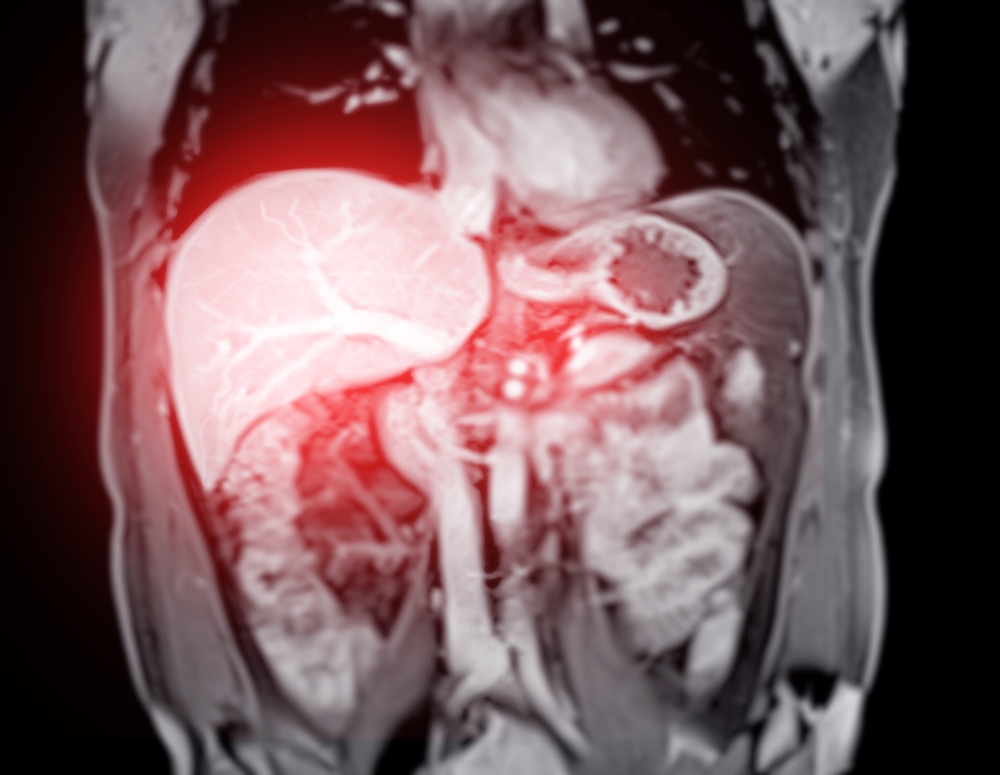

- Magnetinio rezonanso tomografija (MRT) – ypač tiksli vidaus organų vaizdinė analizė